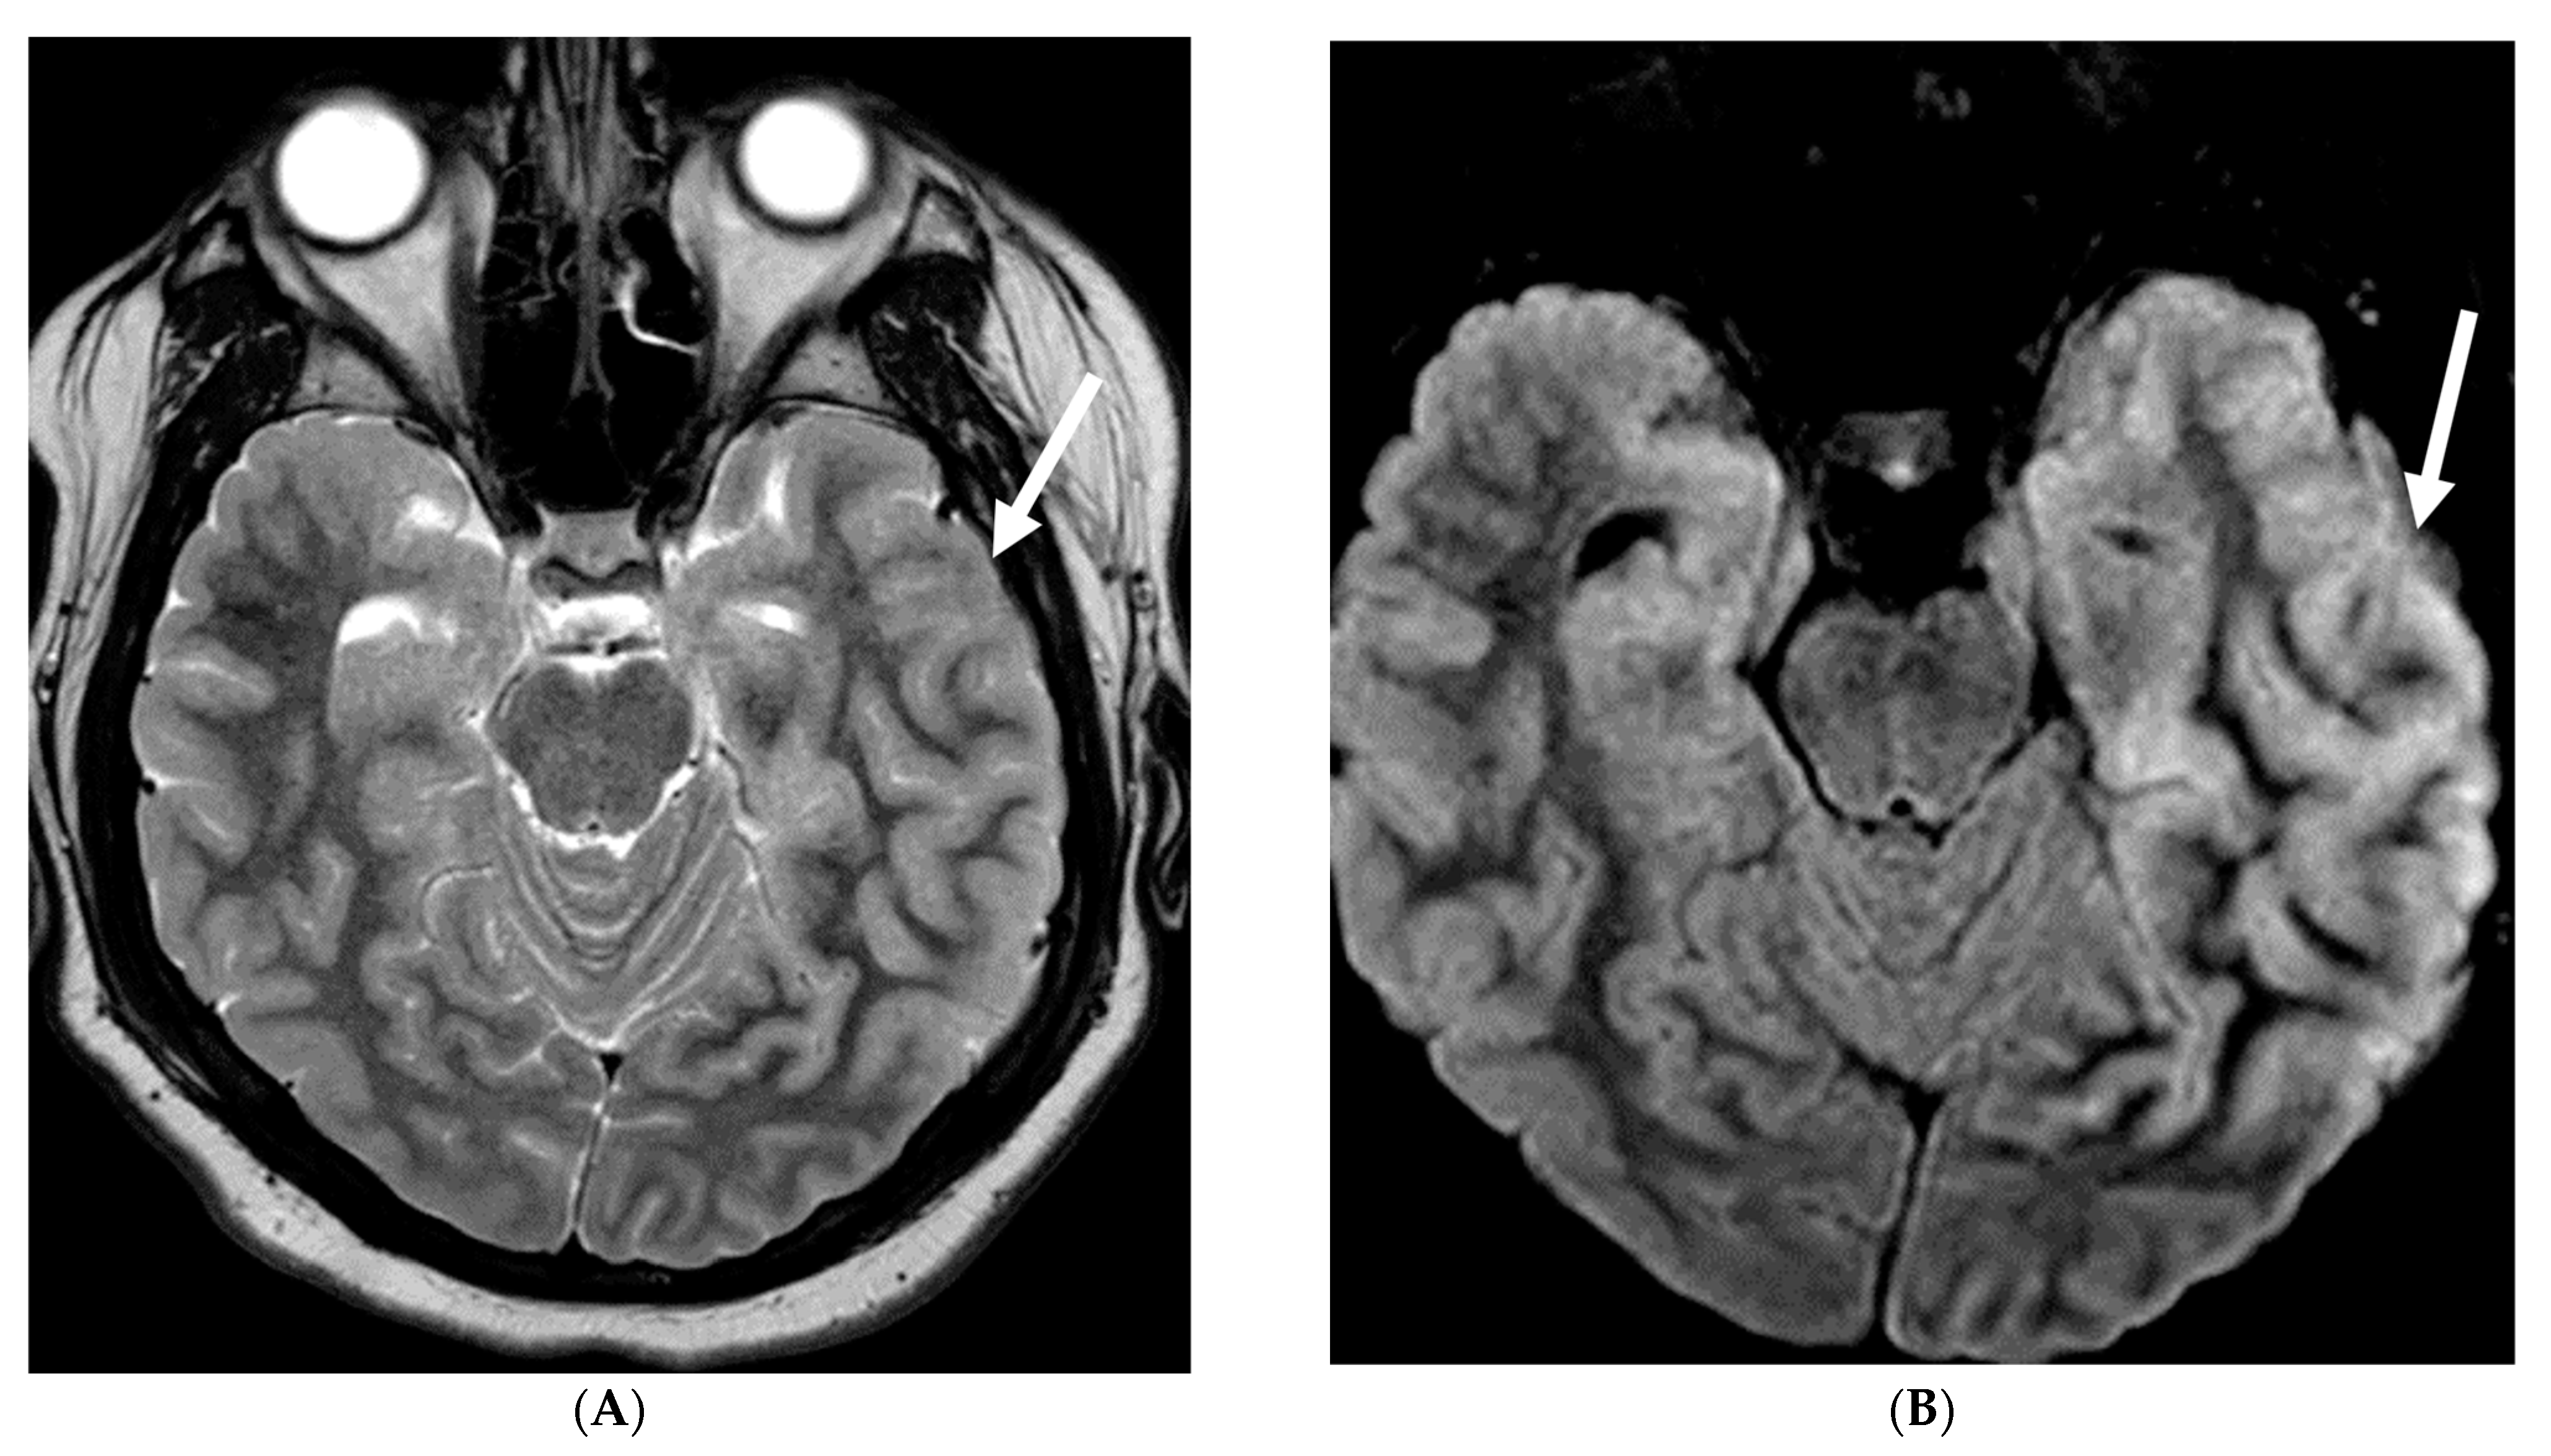

5.2. Fungal Meningitis

Fungal infections of the central nervous system (CNS) can be broadly categorized into two forms based on the causative organism’s size and pathogenesis. Yeast infections (e.g., Cryptococcus, Candida) are smaller and disseminate hematogenously, resulting in parenchymal granulomas, abscesses, and diffuse leptomeningitis. Mold infections (e.g., Aspergillus, Mucorales) are larger fungi that are restricted from entering the meningeal microcirculation, leading to more focal disease manifestations such as cerebritis, abscess formation, vasculitis, infarct, and mycotic aneurysm [99]. Candida is the most common fungal organism affecting children, typically in preterm and/or low birth weight neonates [100]. The routes of CNS invasion by fungal pathogens include hematogenous dissemination from a distant source (commonly lung), direct inoculation following trauma or neurosurgical procedures, and local extension from adjacent structures like the paranasal sinuses, orbit, or spine [101].

MRI findings in fungal meningitis include LME, which can be smooth or thick, nodular and irregular, and commonly involve the cortical sulci [102]. While a smooth, linear enhancement pattern is common in viral and bacterial meningitis, it can also be seen in immunocompetent patients with fungal meningitis [102]. Inflammatory exudates containing cell debris, fibrin, and hemorrhage can deposit in the subarachnoid space, leading to arachnoiditis. Protein accumulation in the subarachnoid space shortens T1 relaxation time and results in increased signal intensity on FLAIR sequences [102]. Meningeal adhesions can obstruct arachnoid granulations, leading to impaired cerebrospinal fluid (CSF) drainage and secondary hydrocephalus. Fungal brain abscesses typically demonstrate a central T1 hypointense and T2 hyperintense core, surrounded by a T1 iso-to-hyperintense and T2 hypointense enhancing peripheral rim (Figure 20) [103,104].

Figure 20.

Axial T2 (A), axial DWI (B), axial SWI (C) and axial T1 post contrast (D): 4-year-old girl with acute lymphoblastic leukemia, pancytopenia and fever. Treatment started one week before with asparaginase. There is prominently T2 hyperintensity and swelling of the gyri involving the medial aspect of the left parietal occipital cortex (arrow). Multiple small foci of T2 hypointensities are identified within the involved region with corresponding blooming on the susceptibility indicating hemorrhage (curved arrow) and peripheral rim of true restricted diffusion (dashed arrow). Postcontrast images show pachymeningeal and LME in the involved region (open arrows). Features are concerning for fungal infection. Pathology revealed Rhizomucor pusillis (thermophilic fungus).